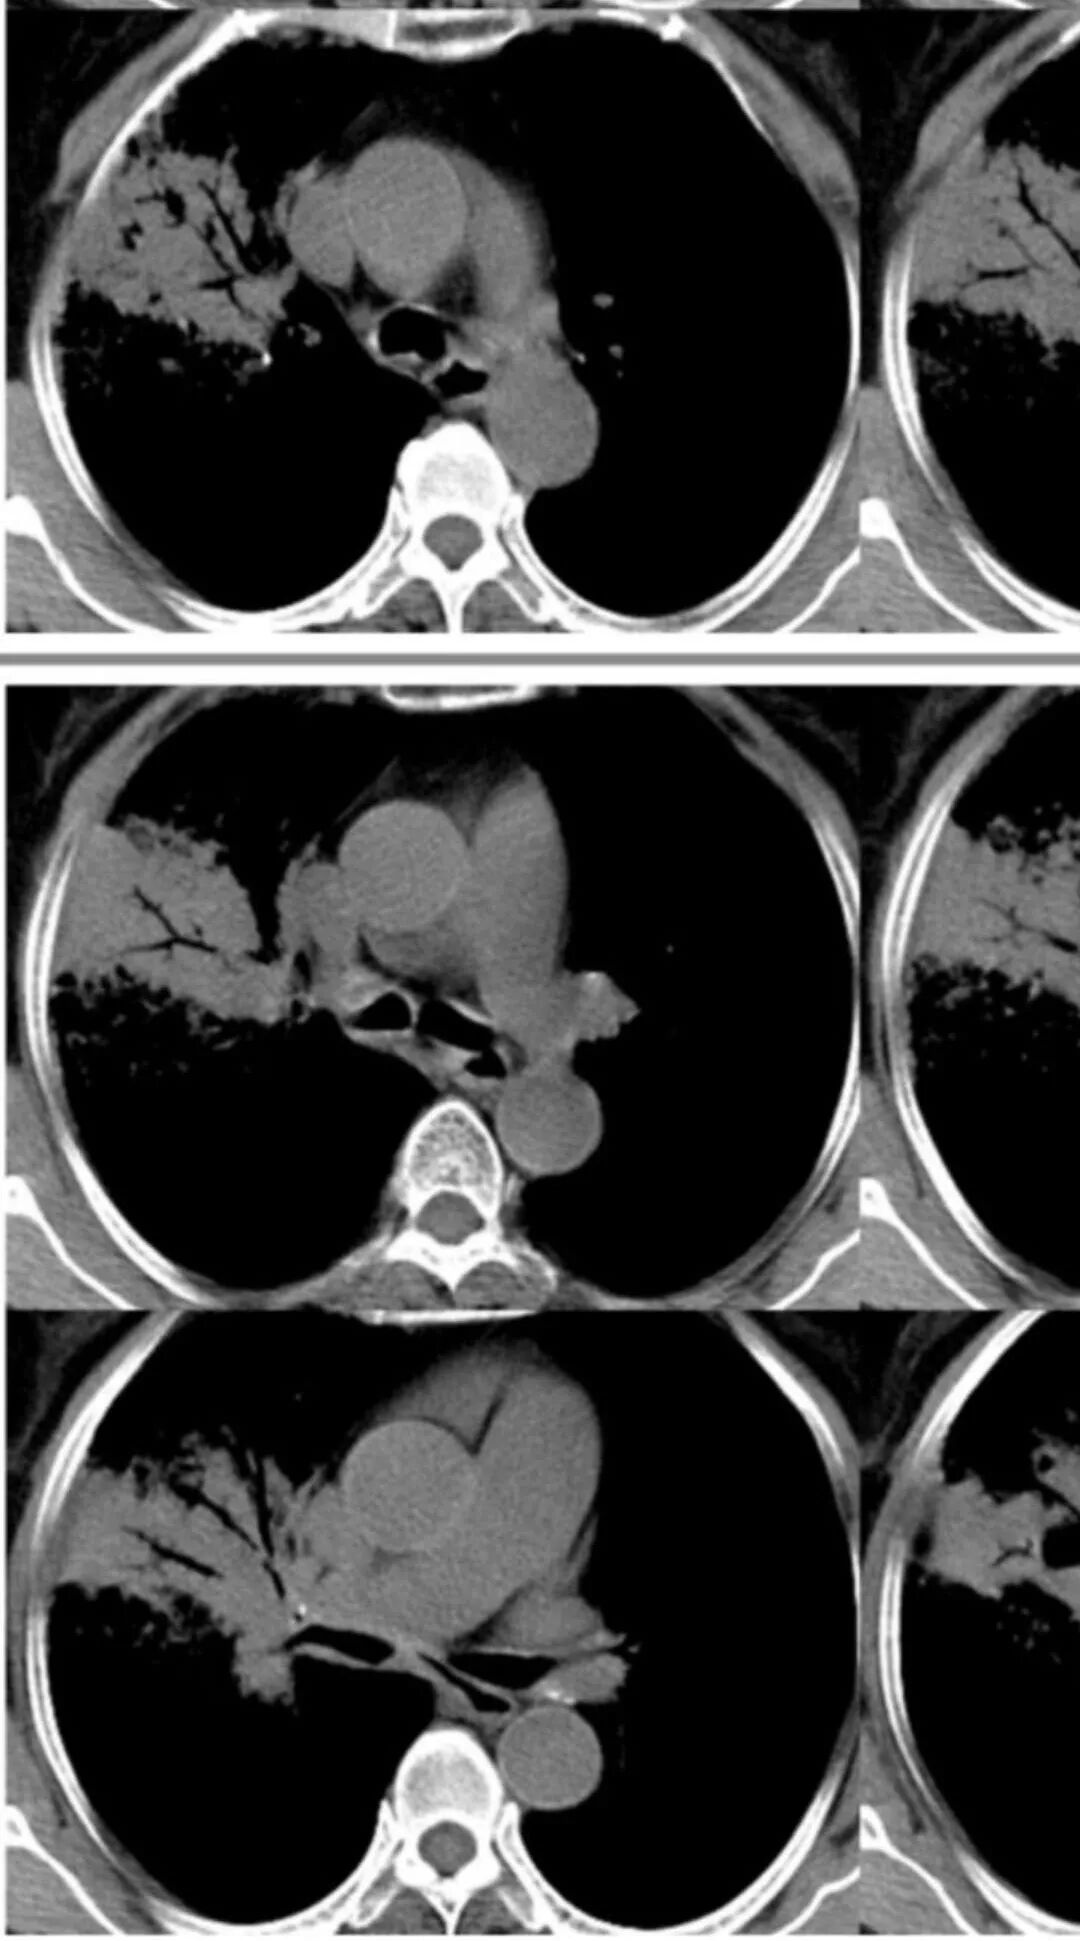

胸CT:右肺上叶实变内可见支气管充气征,近端支气管狭窄,远端扩张,周围可见毛玻璃影,右肺中叶支气管闭塞,并可见气道壁钙化,右肺中叶体积缩小,实变内可见空洞,并可见气液平面,空洞周围可见毛玻璃样影,右肺下叶支气管开口狭窄,右肺门淋巴结肿大。纵隔窗可见病灶与壁层胸膜间隙增宽,考虑良性病变-----感染性病变------TB?

右中叶支气管完全阻塞伴厚壁空洞,右上叶支气管不全阻塞伴大片GGN,右下部分GGN考虑腺鳞癌,结核待排。

老年女性,慢性病程,咳嗽伴白色粘液痰,无发热腹痛,糖尿病,白细胞及C反应蛋白不高,血沉快,铁蛋白高。胸部CT,右肺上叶大片状实变伴磨玻璃密度影,边界不清,边缘局部膨隆,叶裂弧形下坠,实变影宽基底与胸膜相贴;右肺下叶前基底段见类似病灶;右肺中叶不张并空洞形成,空洞内见气液平面;综合考虑右肺上叶及下叶肺炎型肺癌,右肺中叶结核。

这些层面的支气管我觉得像结核的狭窄后扩张,

中叶的体积缩小,也不是粘液腺癌能完全解释,